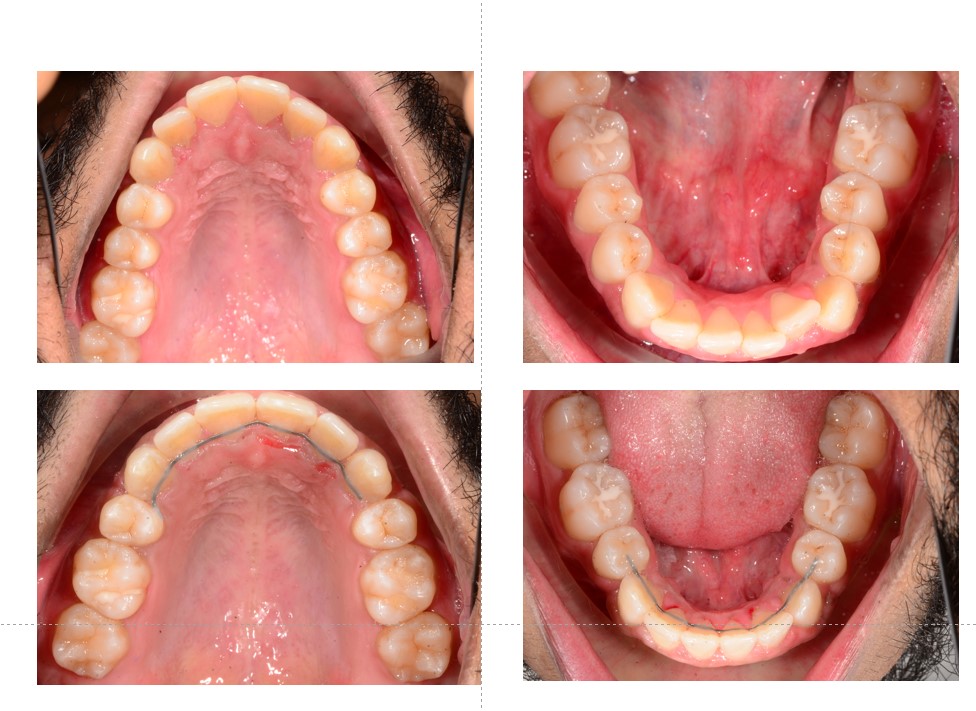

Treatment Results-Before & After

Mar’22 to Dec’24(Timeline)

Dental Improvements

- Full resolution of crowding

- Proper space closure with good root control

- Improved overjet and overbite

- Stable Class I occlusion

Before & After-